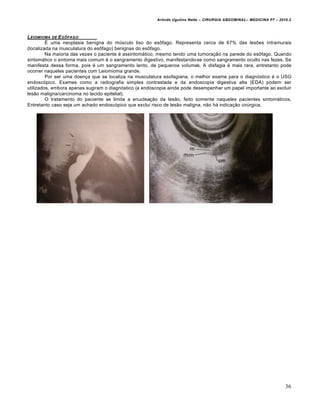

 Exame contrastado de esôfago, estômago e duodeno (EED): imagem caracter„stica com aspecto de mola

espiral ou empilhamento de moedas.